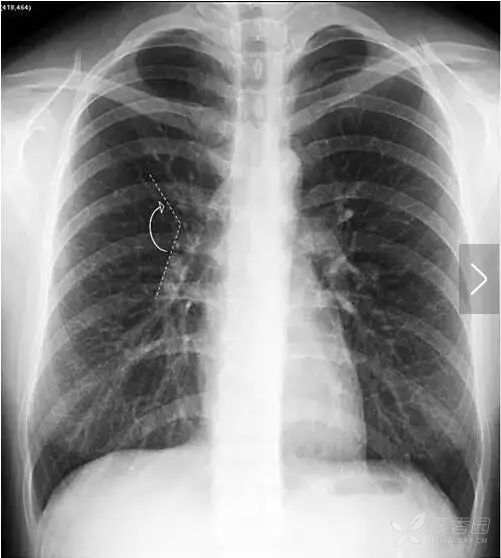

在解剖结构上,肺叶由叶间裂胸膜自然分隔而成,左肺由斜裂分为上、下2个叶,右肺由水平裂(横裂)和斜裂分上、中、下3个叶。胸部X线平片中,叶间裂胸膜和X线方向平行时可以显影,呈细线状。其中,正位胸片常可以看到右肺水平裂(图11)。

图11 右肺水平裂。正位胸片常可以看到细线状的右肺水平裂,位于右肺野中部,自肺野边缘向右肺门水平走行,水平裂以上为右肺上叶,以下为右肺中叶和下叶。